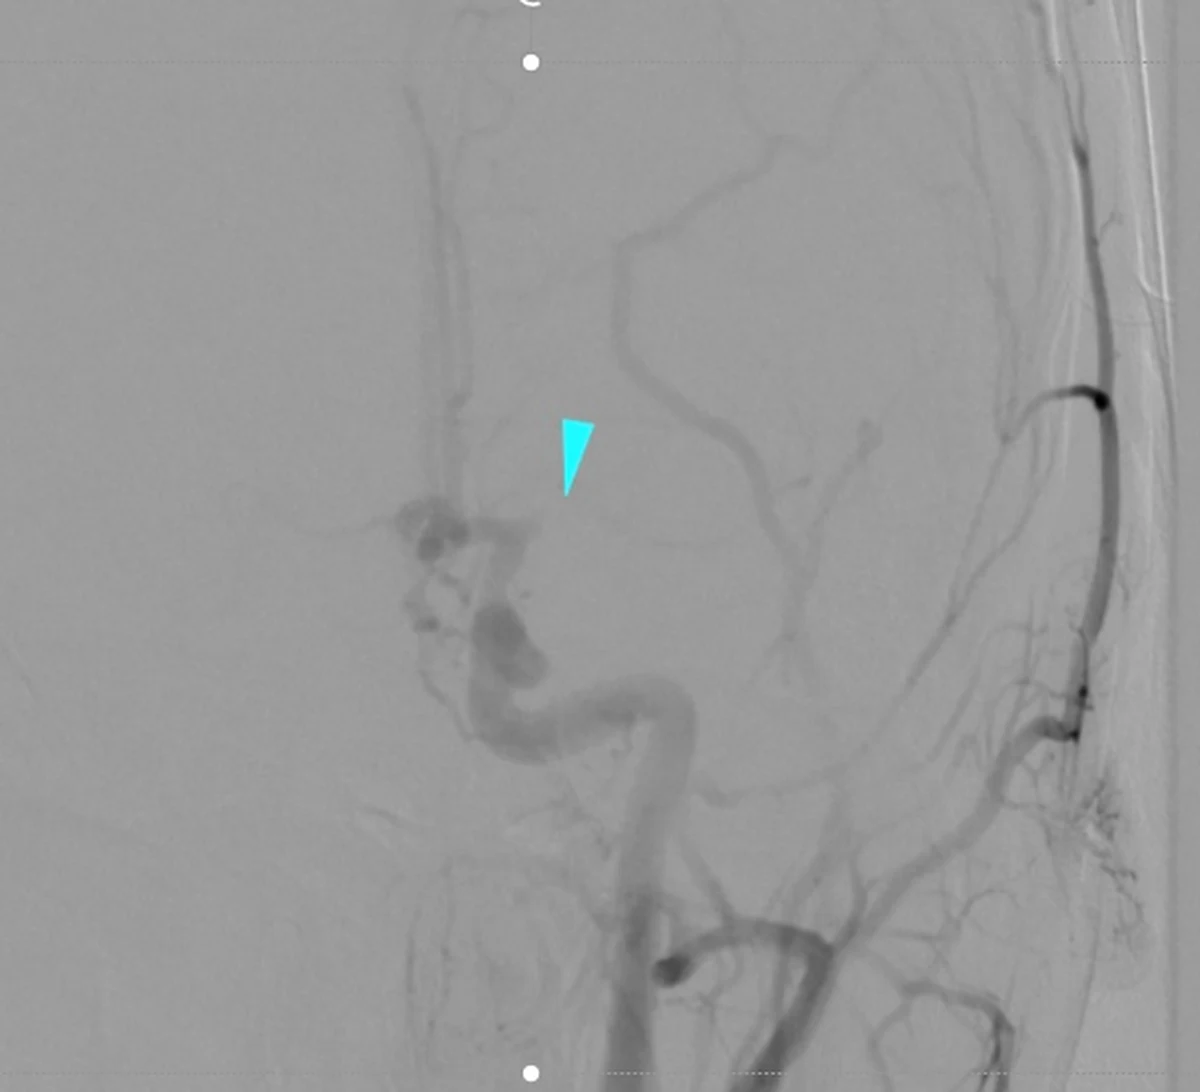

W Wojskowym Instytucie Medycznym w Warszawie, miał miejsce pierwszy przełomowy zabieg leczenia ostrego udaru mózgu u trzynastoletniego dziecka. Pacjent został przywieziony z Ciechanowa. Operacja odbyła się z wykorzystaniem trombektomii mechanicznej - najnowszej metody leczenia udaru niedokrwiennego mózgu, polegającej na instrumentalnym usunięciu skrzepliny z naczynia tętniczego mózgowia.

Lekarze działali w sytuacji „niestandardowej” ze względu na brak istniejących wytycznych co do zasad leczenia zabiegowego, opieki anestezjologicznej i neurologicznej dzieci z udarem mózgu. Ich postawa oraz kreatywne poszukiwanie efektywnych rozwiązań problemu zasługuje na ogromne uznanie. Według udokumentowanych danych jest to drugi lub trzeci przypadek leczenia zabiegowego udaru u dziecka w Polsce. Jest to także najmłodszy pacjent poddany trombektomii w naszym kraju - dodają autorzy komunikatu.